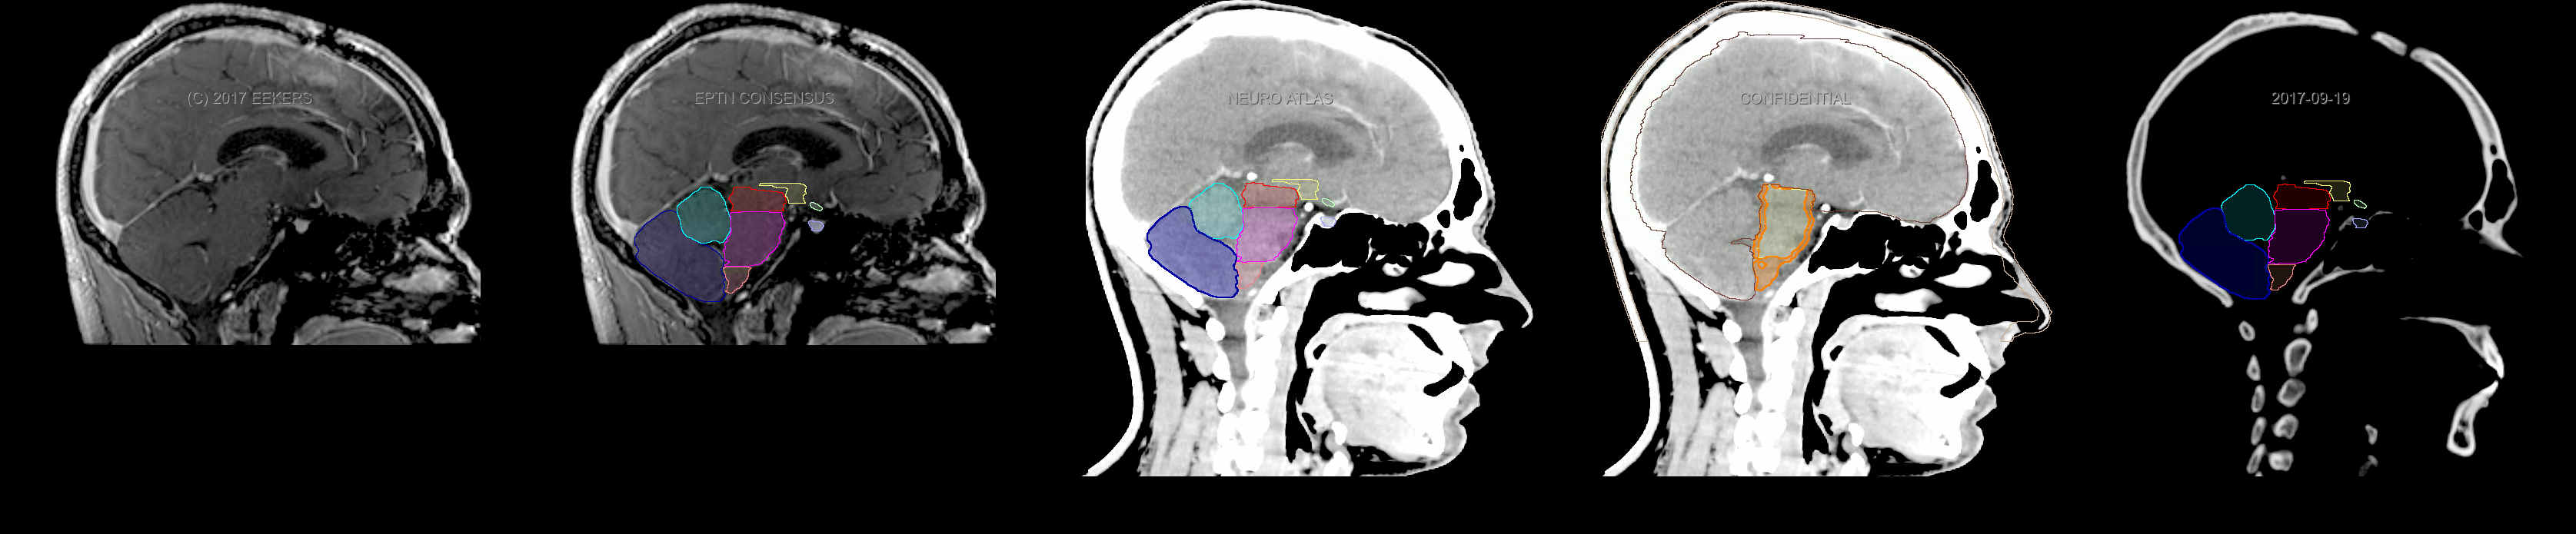

Eekers et al. have published an international neurological atlas for contouring of organs at risk in consensus with the European Particle Therapy Network (EPTN). The purpose of this consensus atlas is to decrease inter- and intra-observer variability in delineating OARs relevant for neuro-oncology. We propose this atlas is used in photon and particle therapy in order to derive consistent dosimetric data. When required this atlas will be updated according to new insights.

Included are all OARs known to be relevant for radiation-induced toxicity in neuro-oncology: brain, brainstem, cochlea, vestibulum & semicircular canals, cornea, lens, retina, lacrimal gland, optic nerve, chiasm, pituitary, hippocampus and skin. A new OAR relevant for neuro-cognition, the posterior cerebellum is also included.

Three-dimensional delineation of the fifteen consensus OARs for neuro-oncology are shown on CT and 3 Tesla (3T) MR images (slice thickness 1 mm with intravenous contrast agent). All are presented in transversal, sagittal and coronal view.

From left to right: MR without structures, MR with structures, CT (WW/WL 120/40) with structures, CT (WW/WL 120/40) with Brain and Brainstem Surface, CT (WW/WL 1500/120)with structures